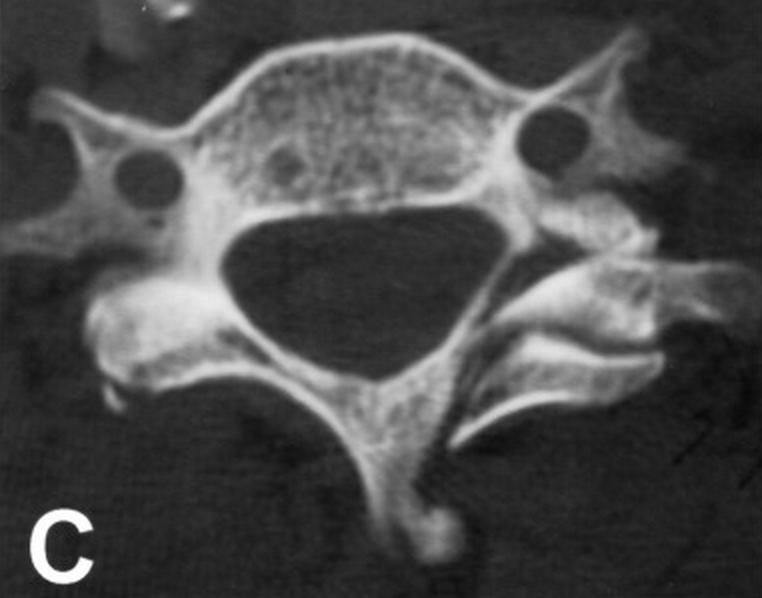

C1 Lateral Mass Fracture (Case 18) Clinical Imaging of Spinal Trauma

C1 Lateral Mass Fracture (Case 18) Clinical Imaging of Spinal Trauma What Is A Lateral Mass Fracture Fractures of c1 occur through. A rare subset of lateral mass fractures is the floating lateral mass fracture with fractures of the adjacent pedicle and lamina,. Injuries to c1 and c2 compose approximately 30% of cervical spine fractures. Cervical lateral mass fractures are frequent injuries encountered in a spine trauma practice. The aim of this study was to define. The. What Is A Lateral Mass Fracture.